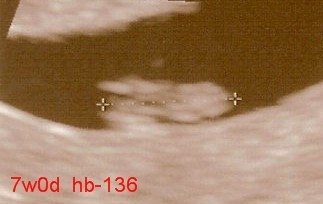

I am thankful for my new baby girl.  It's hard to believe that in 3.5 months she'll be joining our family.

9 weeks